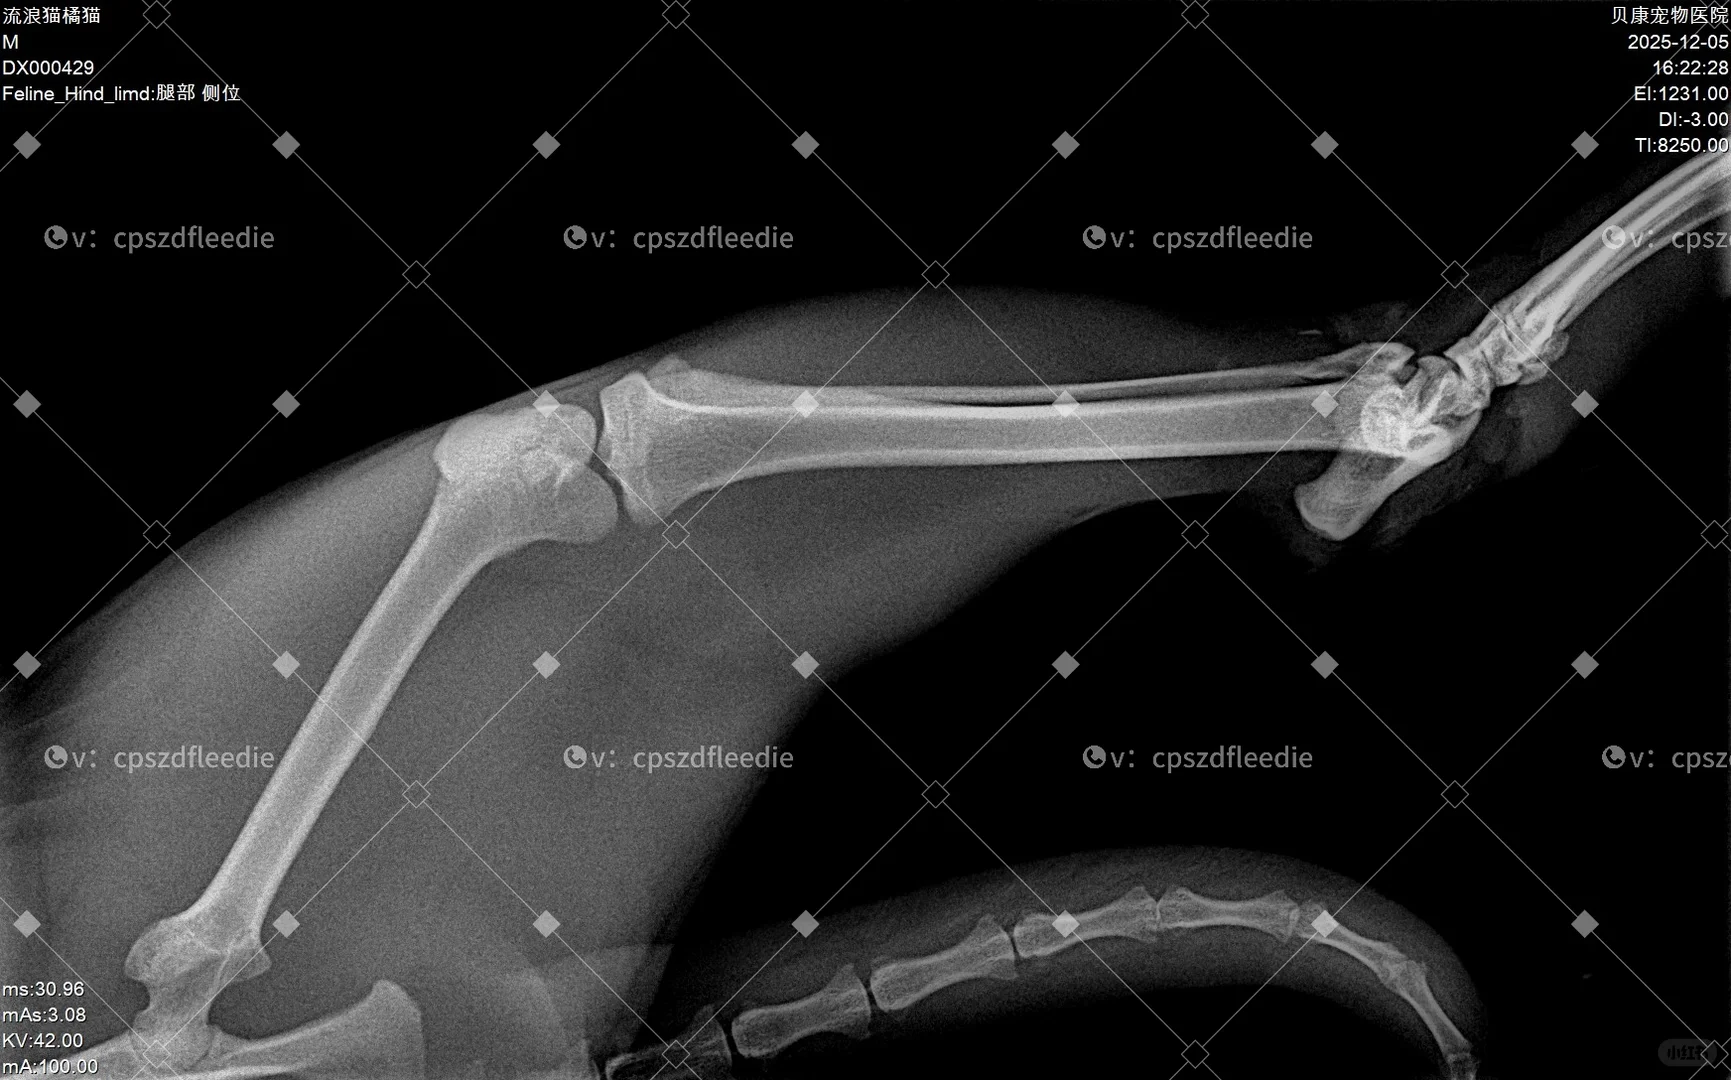

目前情况:一条后腿骨折+神经断了两根,尾巴尖部截肢,先付了外伤处理+住院一周的费用770r。医生说目前不建议做骨折手术,原因是骨折部位离关节很近,并且外伤面积过大,非常容易感染,肉里面都是灰尘。